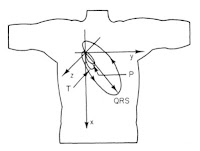

1. Figure 7.16. This picture of the direction of the dipole during the cardiac cycle nicely summarizes the electrocardiogram. My career has focused on the bioelectric behavior of the heart, so it is fitting that my top pick builds on that theme. The reason I chose it, however, is because it was on the cover of the first edition of IPMB, which I used in my first medical physics course taught by John Wikswo at Vanderbilt University.